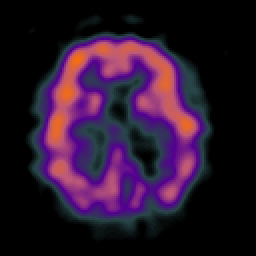

Alzheimer's disease: Perfusion SPECT -- Slice #30

[Home][Help][Clinical][Tour 1][Tour 2] Slice 30